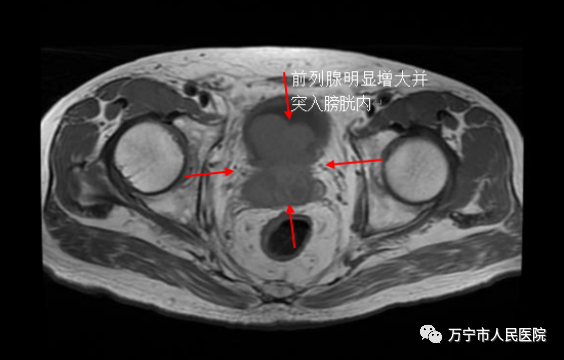

近日,一名78岁老年男性,因“尿频、尿急、尿不尽、遗尿半年”入院,经磁共振等相关检查发现,其前列腺明显增大且突入膀胱内,但因患者同时患有脑梗塞等多种疾病,无法耐受外科手术治疗,经我院介入诊疗科会诊后,在结合患者实际病情下,建议进行双侧前列腺动脉介入栓塞术。

术前磁共振检查显示患者前列腺明显增大且突入膀胱内